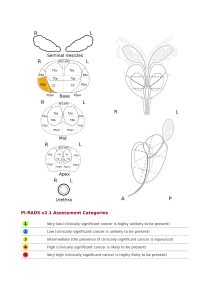

Η περαιτέρω χρήση από το διαγνωστικό μας κέντρο του λογισμικού της Advantis Brainance MD, μας δίνει τη δυνατότητα να εντοπίζουμε ακόμα μικρότερες ύποπτες εστίες, να μελετάμε την αιμοδυναμική τους συμπεριφορά και να αναλύουμε σημαντικές παραμέτρους με στόχο την ακριβέστερη ταξινόμηση των ύποπτων περιοχών κατά TI-RADS. Επισυνάπτεται δε, στον κλινικό ιατρό, λεπτομερής τοπογραφική παρουσίαση των ύποπτων εστιών, με στόχο τον ακριβέστερο προσδιορισμό του σημείου / των σημείων της βιοψίας.